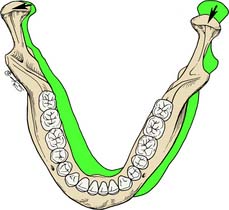

Oral habits consisting of involuntary rhythmic or spasmodic nonfunctional gnashing, grinding, or clenching of teeth, in other than chewing movements of the mandible, that may lead to occlusal trauma is known as bruxism (Fig. 4-18). This activity may be diurnal, nocturnal, or both. Although bruxism is initiated on a subconscious level, nocturnal bruxism is potentially more harmful because the patient is not aware of it while sleeping. Therefore, it can be difficult to detect, but it should be suspected in any patient exhibiting abnormal tooth wear or pain. The prevalence of bruxism is about 10% and is less common with age.18 The etiology of bruxism is often unclear. Some theories relate bruxism to malocclusion, neuromuscular disturbances, responses to emotional distress, or a combination of these factors.19 A study on cohort twins has demonstrated substantial genetic effects20; the condition has been related to sleep disturbance21; and the symptoms of bruxism are three times more common in smokers.22 Altered mastication has been observed in subjects who brux23,24 and may result from an attempt to avoid premature occlusal contacts (occlusal interferences). There may also be a neuromuscular attempt to “rub out” an interfering cusp. The fulcrum effect of rubbing on posterior interferences creates a protrusive or laterotrusive movement that can cause overloading of the anterior teeth, with resultant excessive anterior wear. It is common for wear on anterior teeth to progress from initial faceting on the canines to the central and lateral incisors. Once vertical overlap diminishes as the result of wear, posterior wear facets are commonly observed. However, the chewing patterns of normal subjects can be quite varied, and the relationship, if any, between altered mastication and occlusal dysfunction is not clear.25

Fig. 4-18 Extensive abrasion (tooth wear) resulting from parafunctional grinding.

(Courtesy of Dr. M. Padilla.)